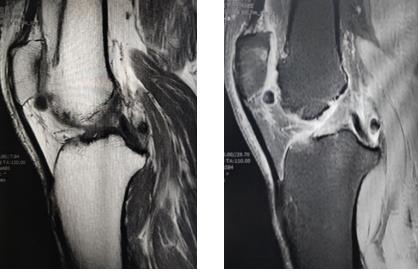

图示膝关节MRI矢状位T1WI及T2WI,应考虑下列哪种疾病

选项:

A: 膝关节结核

B: 滑膜骨软骨瘤

C: 关节游离体

D: 膝关节肿瘤

答案: 【 关节游离体】